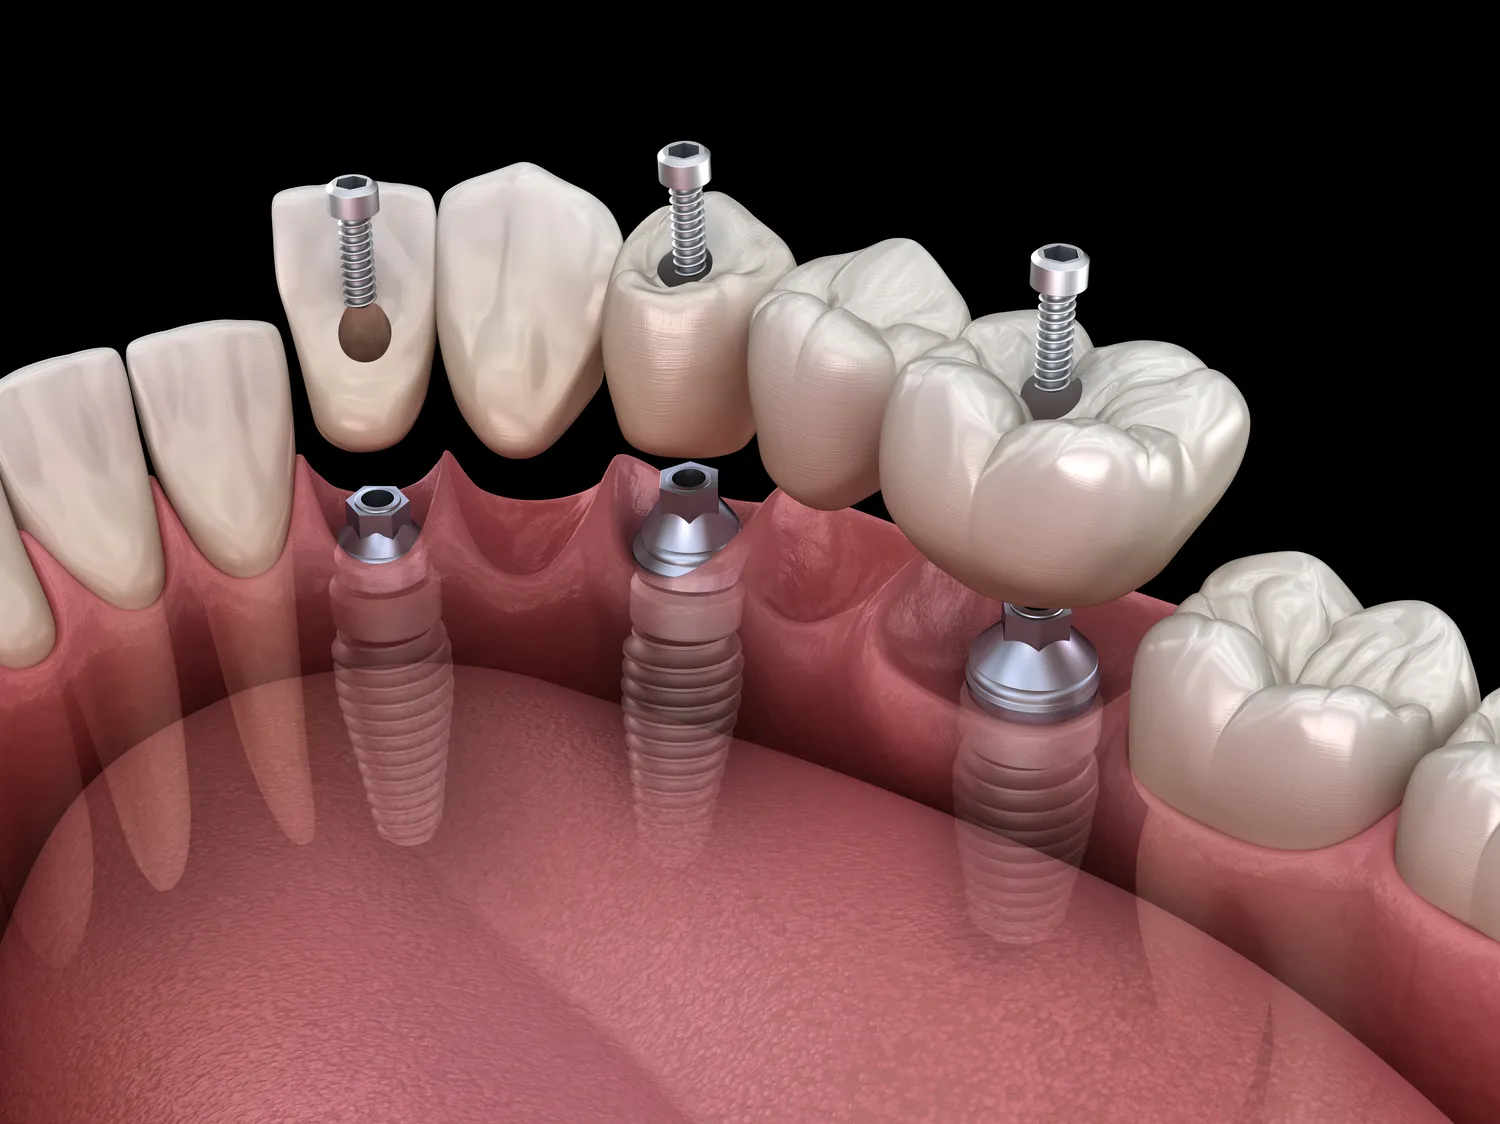

Proces wszczepiania implantów zębów w Warszawie składa się z kilku kluczowych etapów, które mają na celu zapewnienie bezpieczeństwa i skuteczności leczenia. Pierwszym krokiem jest konsultacja stomatologiczna, podczas której lekarz ocenia stan zdrowia pacjenta oraz wykonuje niezbędne badania diagnostyczne, takie jak zdjęcia rentgenowskie czy tomografia komputerowa. Na podstawie tych informacji lekarz podejmuje decyzję o możliwości wszczepienia implantu oraz planuje przebieg zabiegu. Następnie następuje etap chirurgiczny – podczas operacji lekarz wszczepia implant do kości szczęki lub żuchwy. Po zabiegu pacjent musi przestrzegać zaleceń dotyczących pielęgnacji oraz diety przez kilka tygodni, aby umożliwić prawidłowe gojenie się tkanek. Po upływie określonego czasu następuje etap odbudowy protetycznej – na wszczepiony implant zakłada się koronę protetyczną, która przywraca estetykę i funkcjonalność uśmiechu.